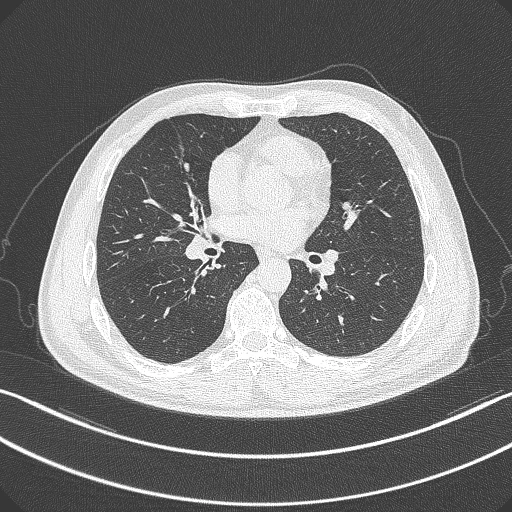

CT scan

Predominantly used in early-stage lung cancer screening, the system started out with a huge stock of digital health records dating back to 2003 and employed technologies from GE Healthcare, Nvidia and Cisco, as well as more than 50 deep learning algorithms, to refine its diagnosis techniques into a tool it calls AI Scholar.

An AI diagnostic tool that's constantly learning and refining its abilities could cut way down on the repetitive work of trawling through scans, chewing through over 100 high-definition Dicom medical images per second, and letting doctors get to more people.